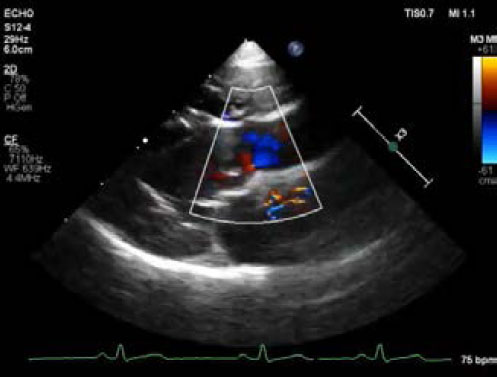

Transthoracic echocardiography (Affiniti 50; Philips Medical Systems, WA, USA) was performed with a sector-array transducer (4–12 MHz). An abnormal slit-like tunnel structure, 2.2 mm in internal diameter, connecting the ascending aorta to the left ventricle was detected above the sinutubular junction. The opening of this structure was located in the base of the ventriculoaortic junction between the anterior mitral leaflet and non-coronary cusp. The morphology and motion of both the mitral and arterial valves were normal, with no evidence of aortic stenosis, mitral regurgitation, or valvular vegetation (Supplementary video I). During the diastolic phase, a regurgitant jet was detected along the aortic cusps with a 2.8 m/second peak velocity and 32 mmHg pressure gradient and along the anterior mitral leaflet with a 2.3 m/second peak velocity and 22 mmHg pressure gradient from the tunnel opening to the left ventricle (Fig. 2, Supplementary Video I). There was mild left ventricular eccentric hypertrophy with an internal diameter in diastole and systole of 23.7 mm (reference range: 16.70–18.93 mm) and 12.2 mm (reference range: 9.04–10.98 mm), respectively. The normalized value of the end diastolic left ventricular interior dimension was 1.63 (reference range: <1.7). The interventricular septum thickness in diastole and systole was 4.9 mm (reference range: 5.70–7.53 mm) and 6.1 mm (reference range: 8.60–10.64 mm), respectively. The thickness of the left posterior wall during diastole and systole was 4.6 mm (reference range: 4.53–6.03 mm) and 7.0 mm (reference range: 7.97–9.55 mm), respectively. Left ventricular systolic function was normal based on fractional shortening of 48.5% and an ejection fraction of 61.6% obtained by Simpson’s method of discs.

Fig. 2. Echocardiography of right parasternal five chamber view (A–C), oblique right parasternal short axis view of the heart base (D), and oblique left apical long axis view (E,F). (A, B) an abnormal slit-like tunnel structure (arrowheads) next to the aorta is shown. (A,C) The opening of this tunnel structure is located in the base of the ventriculoaortic junction between the non-coronary cusps and anterior mitral leaflet. (D–F) during the diastolic phase, a regurgitant jet is detected along the aortic cusps (black arrows; 2.8 m/second peak velocity, 32 mmHg pressure gradient) and along the anterior mitral leaflet (white arrows; 2.3 m/second peak velocity, 22 mmHg pressure gradient) from the tunnel opening to the left ventricle.